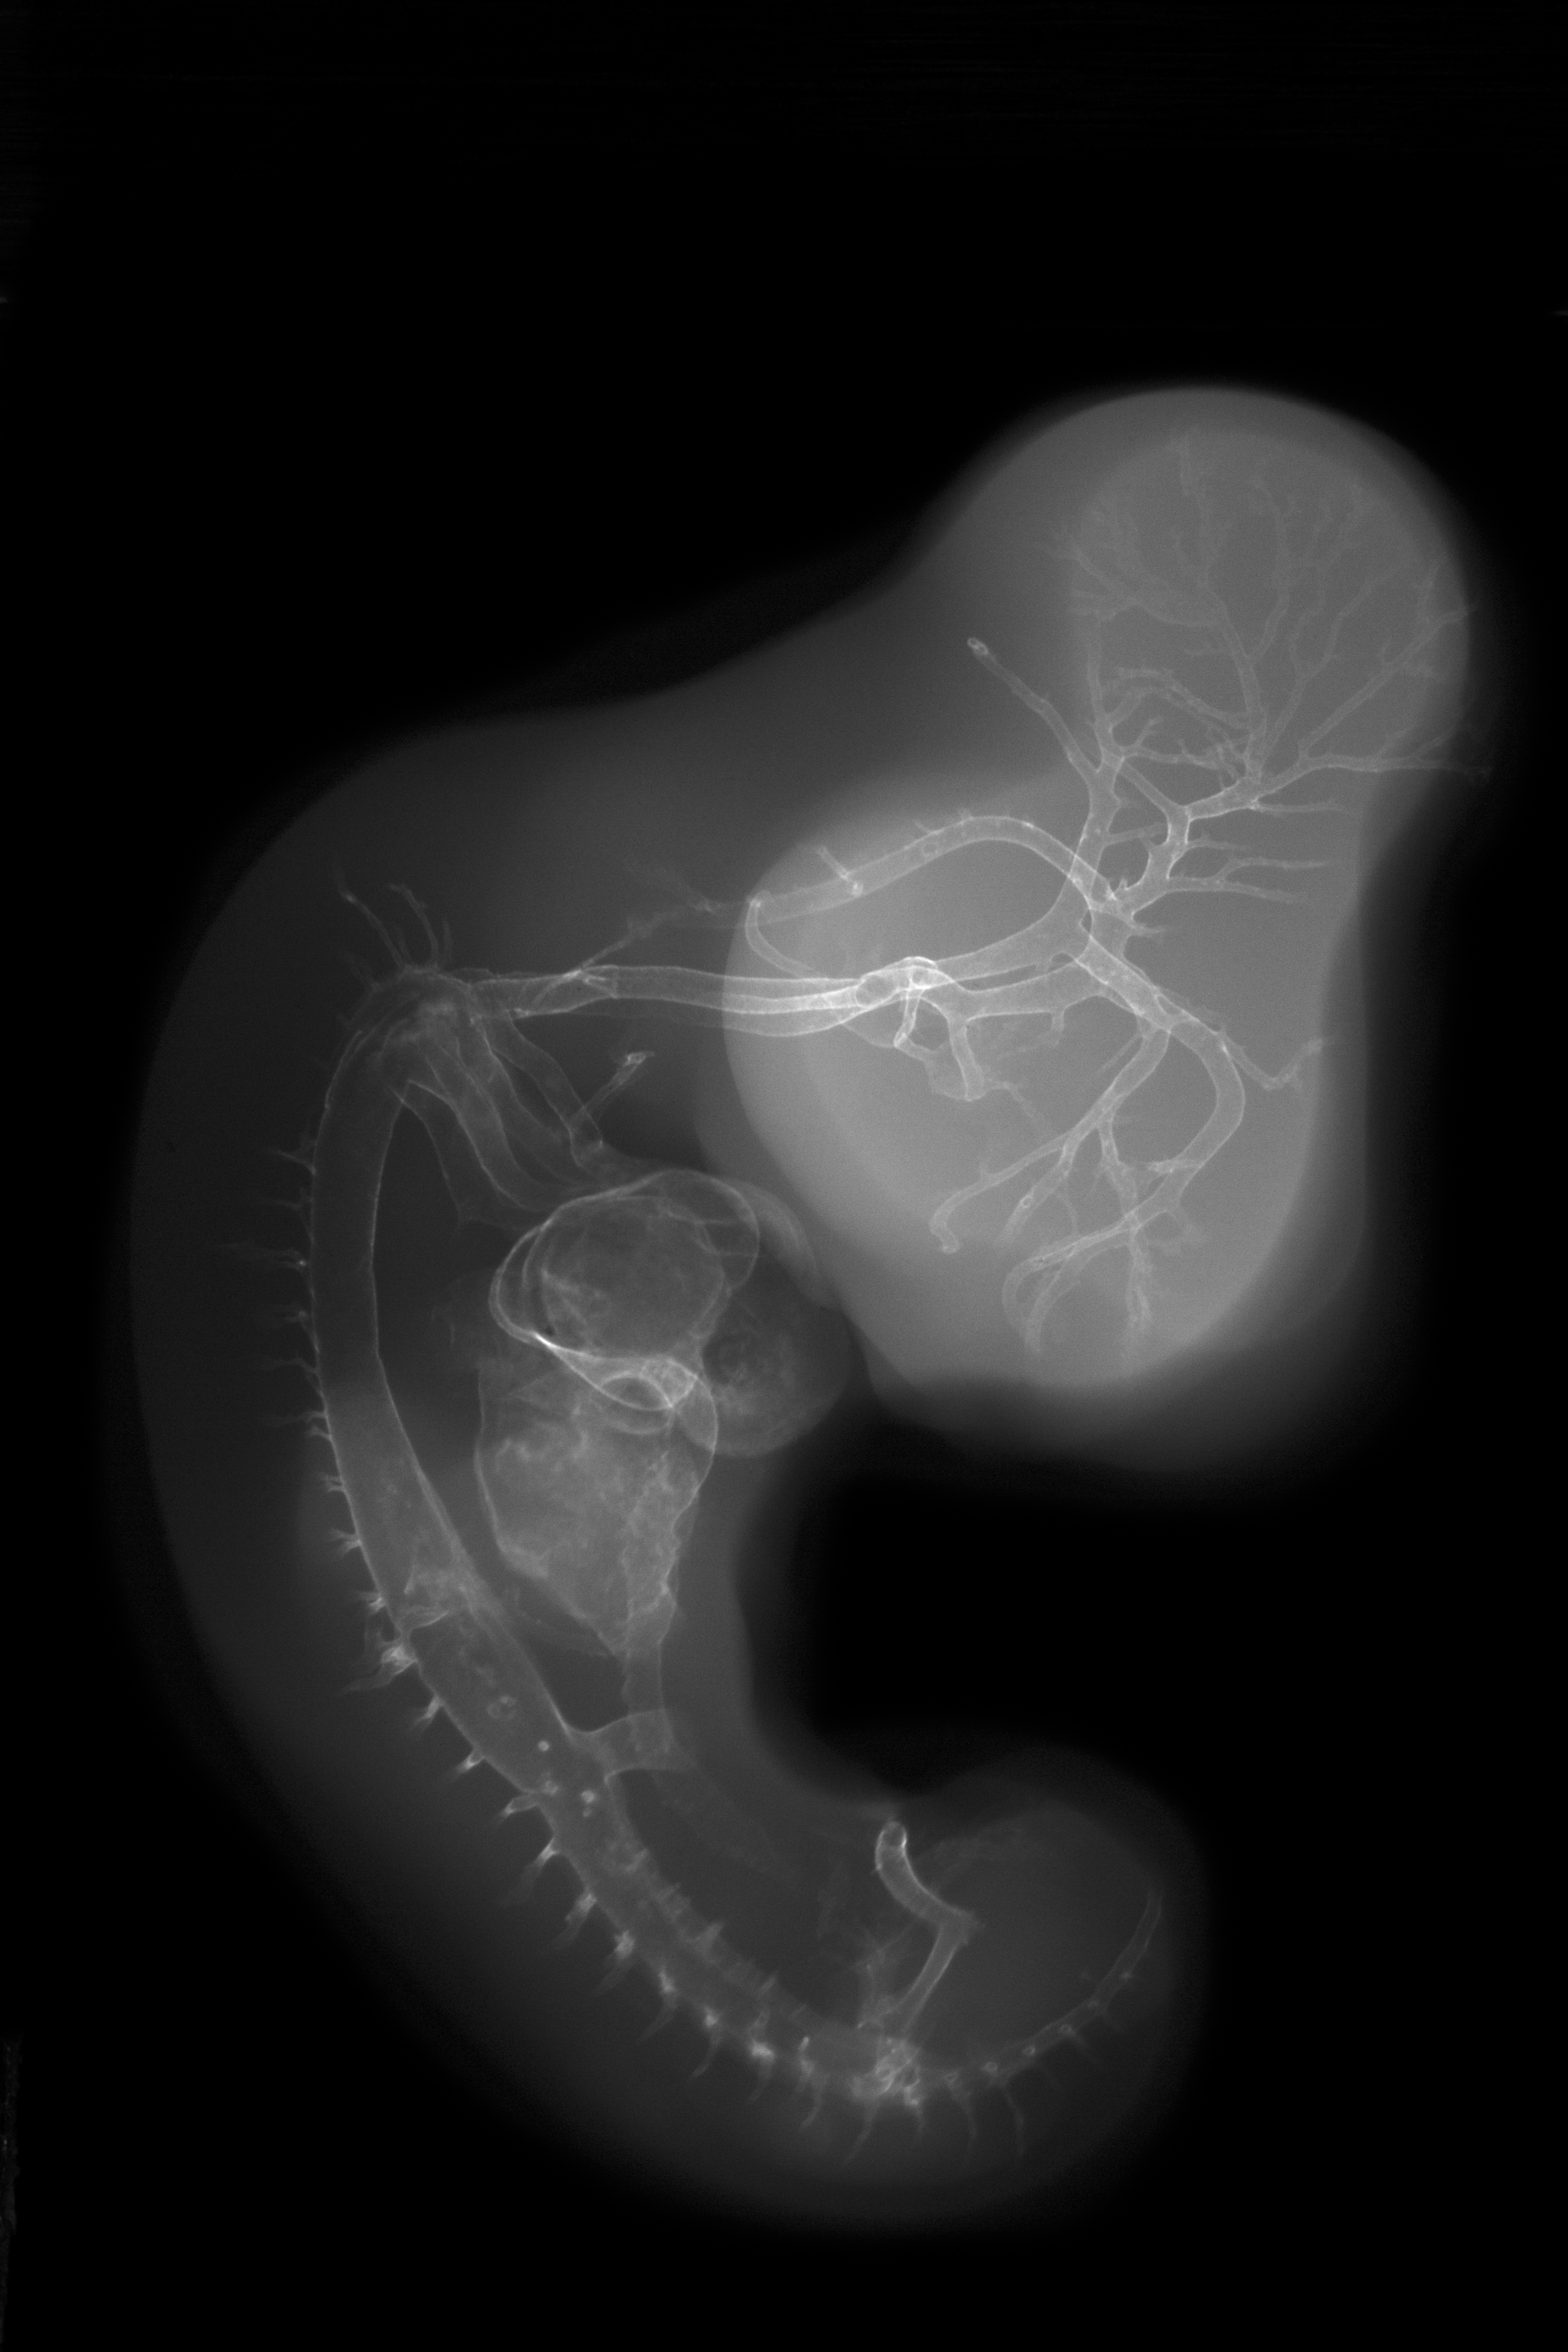

Chick Embryo Microangiography

Hamburger-Hamilton (HH) Stage 26 (approx. 5 days)

X-Ray Micrographs